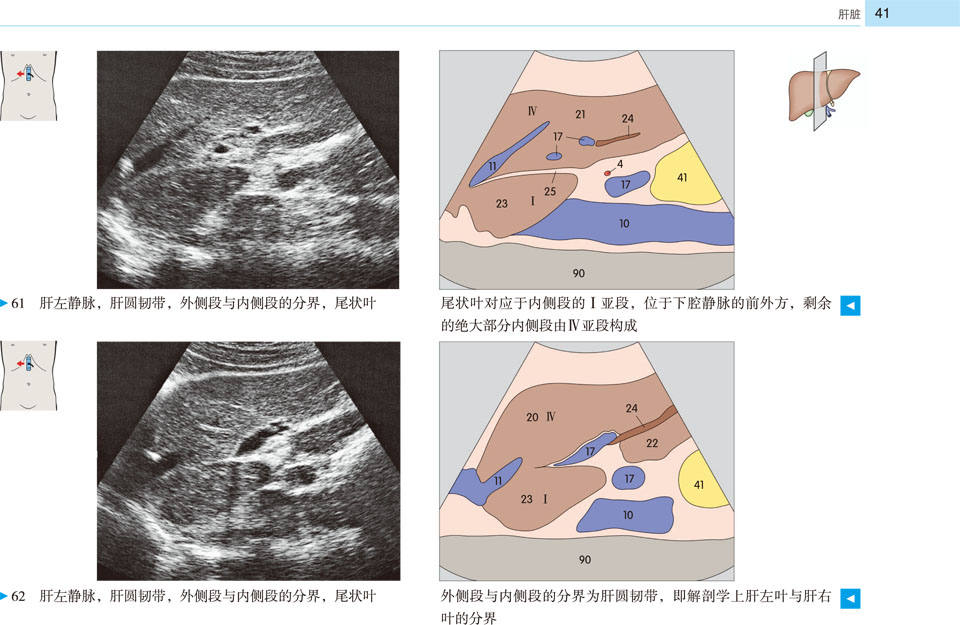

本书提供了全新的、高质量的超声图像和示意图,标示清晰、色彩丰富,为初学者带来极大的帮助。展示了腹部、盆部、甲状腺超声的所有标准切面和扫描路径,标示了各解剖结构和间隙在三维空间的解剖细节及其与超声的关系;并展示了探头定位,以及生成的截面图像、解剖结构、扫描平面在器官中的位置。本书作为优秀的初学者向导,适用于医学生、超声科医师、临床各科医师。